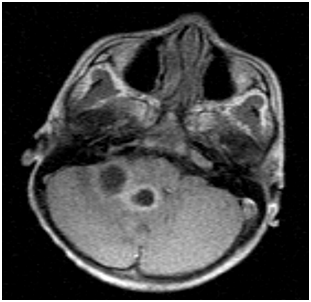

A 6year old boy weighing 14kg (expected weight=20kg) was referred to the neurosurgical unit of University College Hospital, Ibadan, with complaints of headache, vomiting, fever and unsteady gait of one week duration. There was no history of ear ache or ear discharge, scalp infection, trauma, seizure or any other systemic disorder. He was diagnosed to have multiple right cerebellar hemispheric abscesses based on Magnetic Resonance Imaging (MRI) finding of rings enhancing masses in the cerebellum (Figures 1) (Figure 2). He is a known patient of the paediatric Cardiology unit with uncorrected congenital heart defect. Pregnancy birth and neonatal history were uneventful until 5months of age when he was diagnosed with congenital heart disease and has been on follow up until this present illness. He has never been in heart failure and was not on any cardiac medication. Patient was awaiting surgery for the heart defect when he developed this present illness. His physical examination revealed a small for age child, afebrile, not pale, anicteric but has central cyanosis and peripheral oxygen saturation (SpO2) was 85% in room air with grade 2 digital clubbing.

Figure 2 MRI showing multiple cerebellar abscesses.